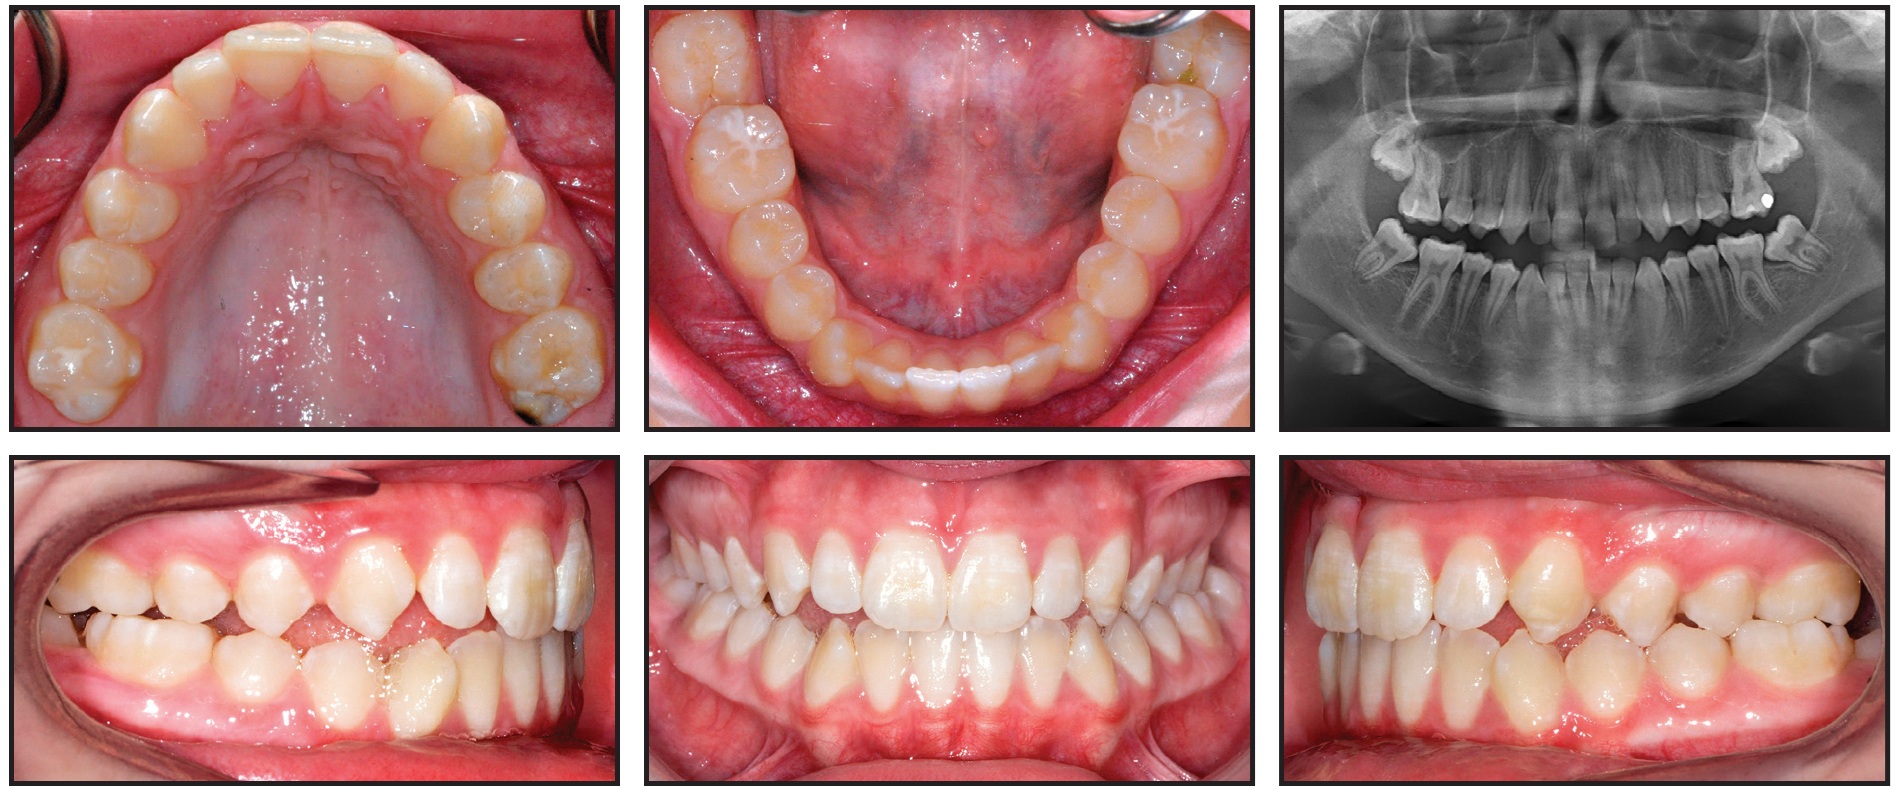

A 13-year-old female presented with the chief complaint of crowded teeth and a lower molar that was “growing in wrong.” She had a straight profile, with a prominent chin and an obtuse nasolabial angle, and she exhibited 90% incisal display on smiling and a normal lower anterior facial height. Further clinical examination showed a Class III subdivision right malocclusion, with MTD leading to constricted maxillary buccal segments (Fig. 1).

Fig. 1 Case 1. 13-year-old female patient with maxillary transverse deficiency, Class III malocclusion, and mandibular deviation before treatment.

The mandibular midline was shifted 2.5mm to the left because of a functional shift of the mandible on closure. An anterior open bite was present in the maxillary right lateral and canine regions. Both mandibular second molars were erupting at a mesial angle.

The panoramic radiograph revealed a root dilaceration of the upper right lateral incisor, normal TMJ anatomy, and no third molar buds. Cephalometric analysis indicated a Class III skeletal pattern with a prognathic mandible, a normal vertical growth pattern, and retroclined mandibular incisors. Cervical vertebral maturation was at stage 4.24 A frontal cephalometric finding of facial asymmetry supported the diagnosis of a functional shift.

A 12-year-old female presented with the chief complaint that “my tooth is coming in a little high.” She had a straight profile with an obtuse mentolabial sulcus, symmetrical face, and thin lips, but she appeared tired because of dark infraorbital circles. The patient showed 100% incisal display on smiling, with 2.5mm of gingival display and wide buccal corridors. We noted a Class I molar relationship, moderate crowding in both arches, and a Class III skeletal relationship due to a prognathic mandible and a slightly low mandibular plane angle (Fig. 6). The patient had a 50% overbite, along with a 2mm maxillary anterior Bolton deficiency. There was inadequate space for the upper canines, which were beginning to erupt. The angulation of the canines was appropriate, however, and no resorption of the lateral incisors was observed.

Fig. 6 Case 2. 12-year-old female patient with Class III skeletal and Class I molar relationships, 50% overbite, and moderate crowding in both arches.

Panoramic radiography revealed enlarged nasal turbinates; all permanent teeth were present, and the third molar buds were developing. Cephalometric analysis indicated retroclined mandibular incisors, slightly proclined maxillary incisors, and a cervical vertebral maturation stage 2.24